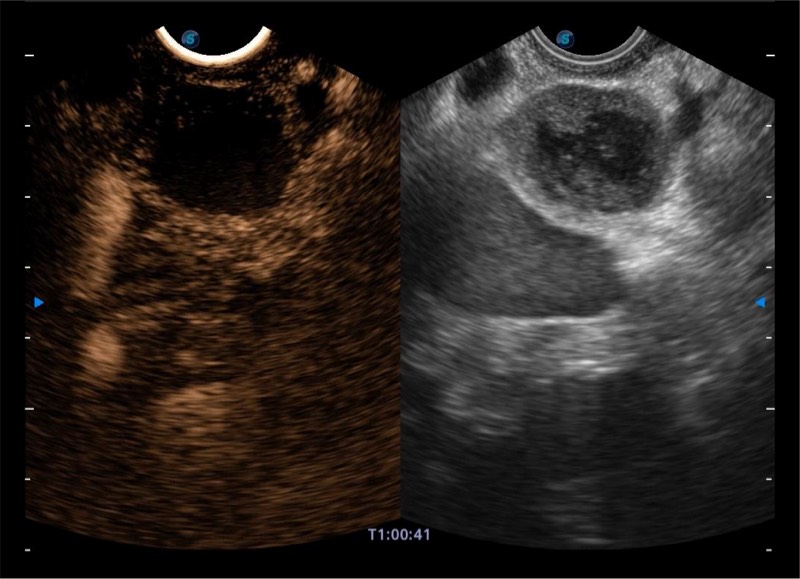

高端超声影像平台

基于二十年的超声技术积累,新葡的京集团8814检测站提供了最新一代的独立超声主机,在提供高质量图像的同时满足多学科使用。具备常见多普勒技术并提供弹性成像、声学造影等高端影像技术。新一代传感器具有更强的抗干扰能力并减少图像伪影。